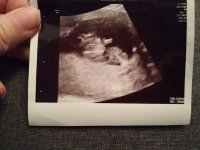

Ultralyd i dag 14+0 ❤